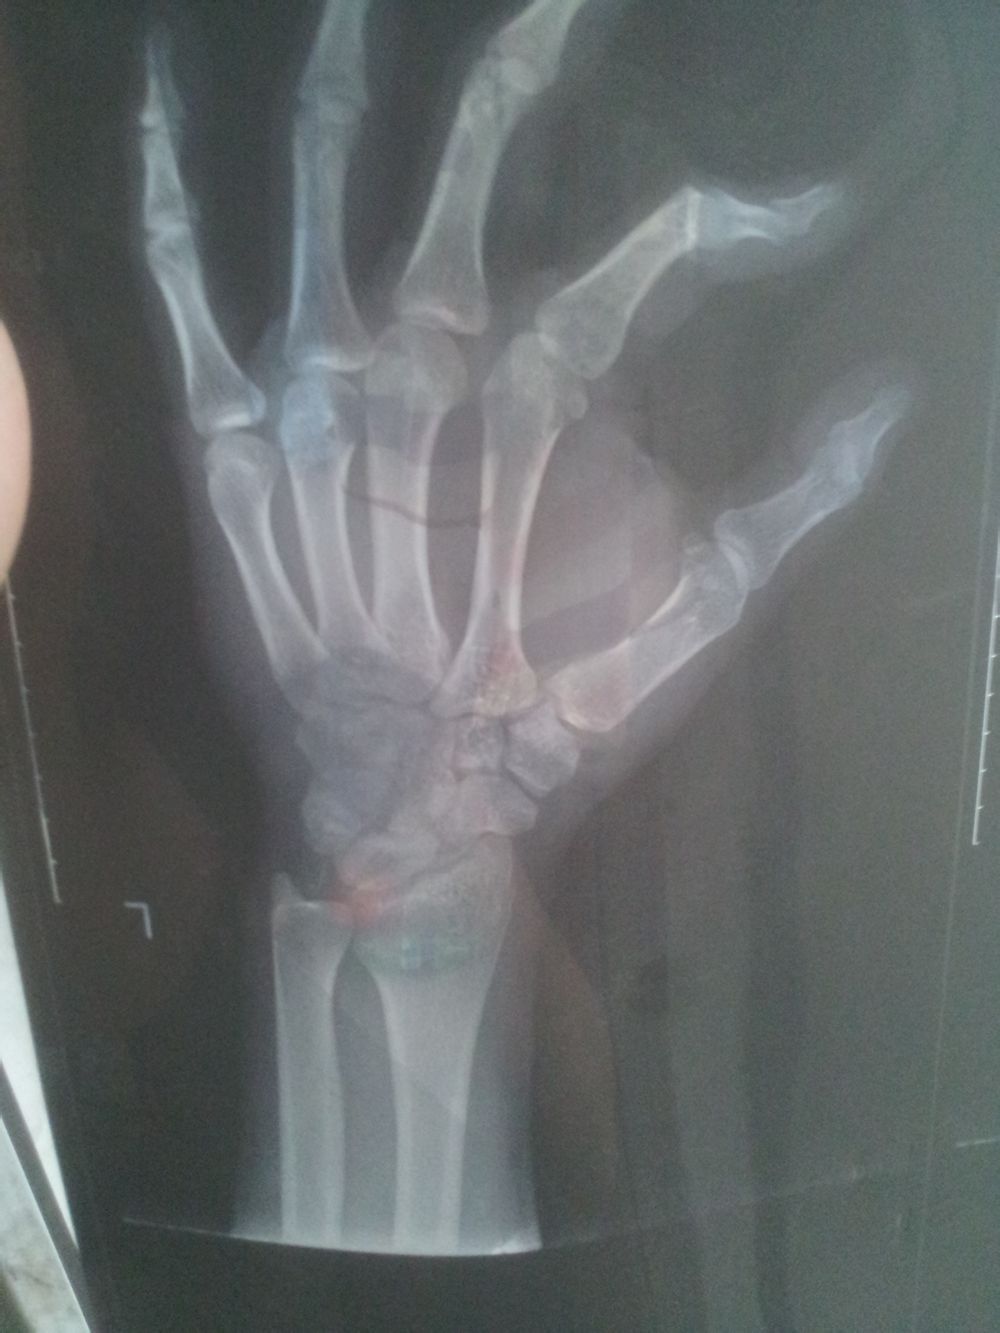

帮我看下

你的手骨怎么不直[疑问]

医生让这么拍的

还有白色的软骨